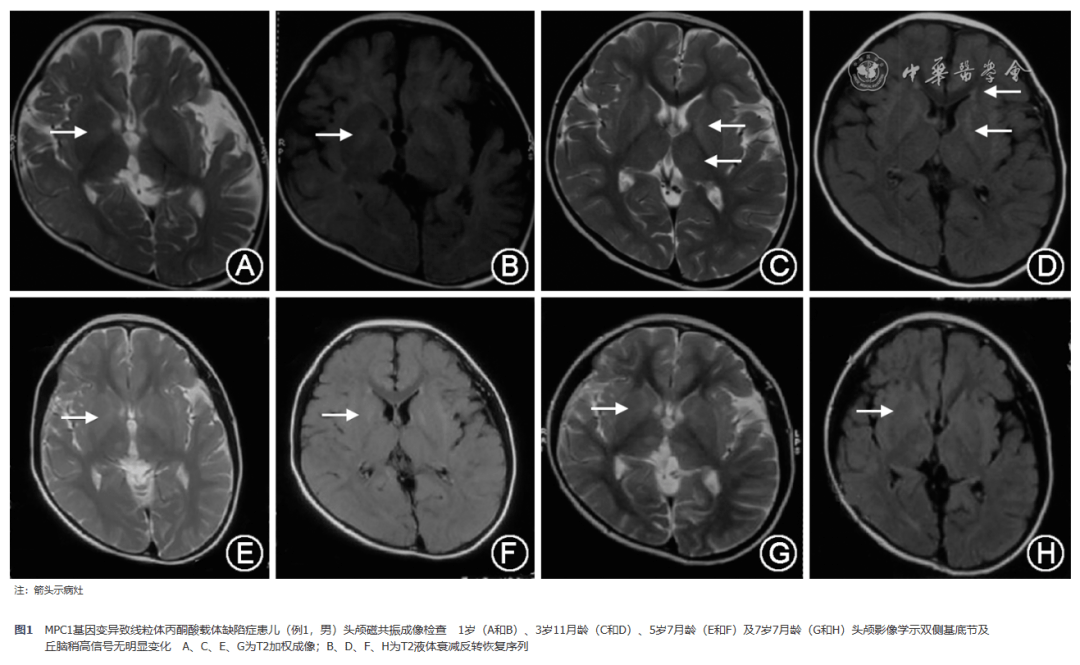

【神经系统疾病研究】线粒体丙酮酸载体缺陷症3例并文献复习

图片尺寸1080x665